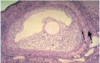

What part of the female reproductive tract is this histological image

The uterine tubes

Describe the structure of the tunica mucosa of the uterine tube?

- Highly folded around the length of the tube.

- Varies from different regions- ampulla is more elaborate folded.

- The isthmus is less elaborately folded

What are the sublayers of the tunica mucosa of the uterine tube?

Epithelium

Basement membrane

Lamina propria

What is the epithelium of the uterine tubes?

Simple columnar epithelium that has two different cell types.

Peg cells (also known as secretory cells).

Ciliated cells